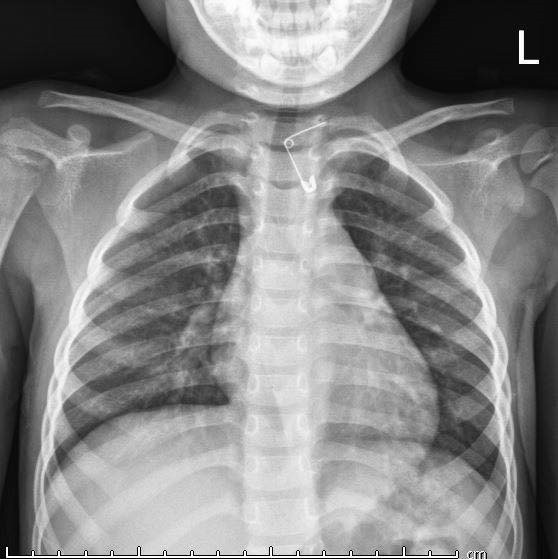

| Vị trí chiếc kim băng nằm trong thực quản bệnh nhi. |